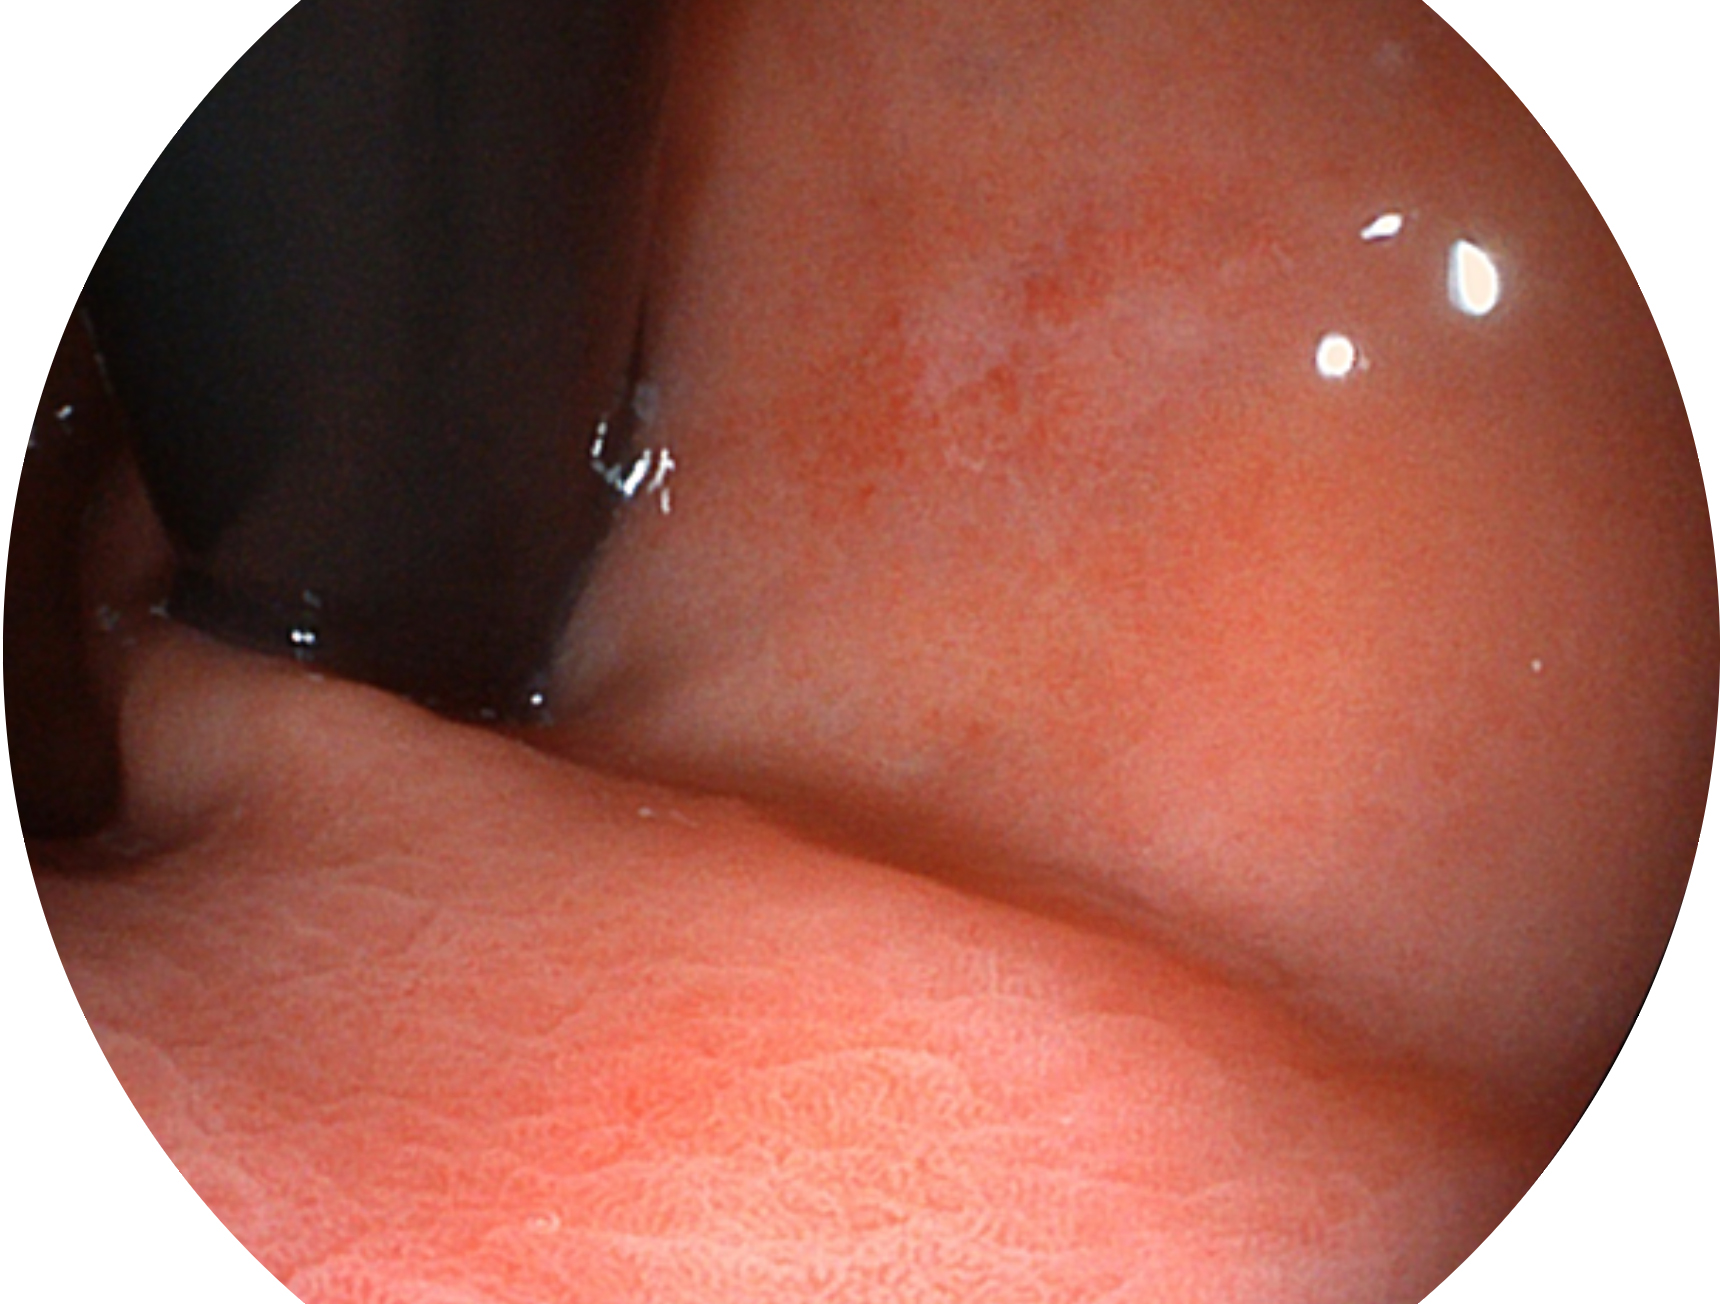

• 白光图像 VIST图像

SFI技术是结合特定光谱照明与数字光谱滤波,实现高亮度特殊光成像。染色模式下,不改变粘液、食物残渣、粪液等基本颜色,在保持与白光照明相似的图像色调的同时突显了图像颜色的红白对比度,且在远距离观察的情况下具备与普通白光模式相同的图像亮度,有助于消化道疾病的大范围扫查和早癌筛查。